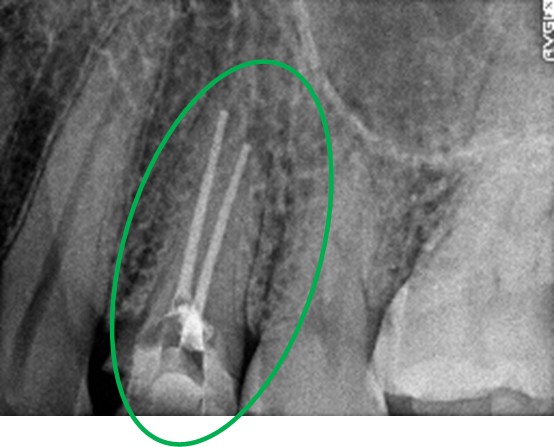

主訴

以前治療した右下の犬歯が、虫歯になり色が変わってきているので、治したい。

治療内容

根管治療をし、オールセラミック冠を被せました。

所感

神経が取り除かれ、歯自体が変色し、虫歯になっていました。根管治療をし、ファイバーコアを入れ、オールセラミック冠を被せました。

オールセラミック冠1本(失活歯):¥104,500(税込)